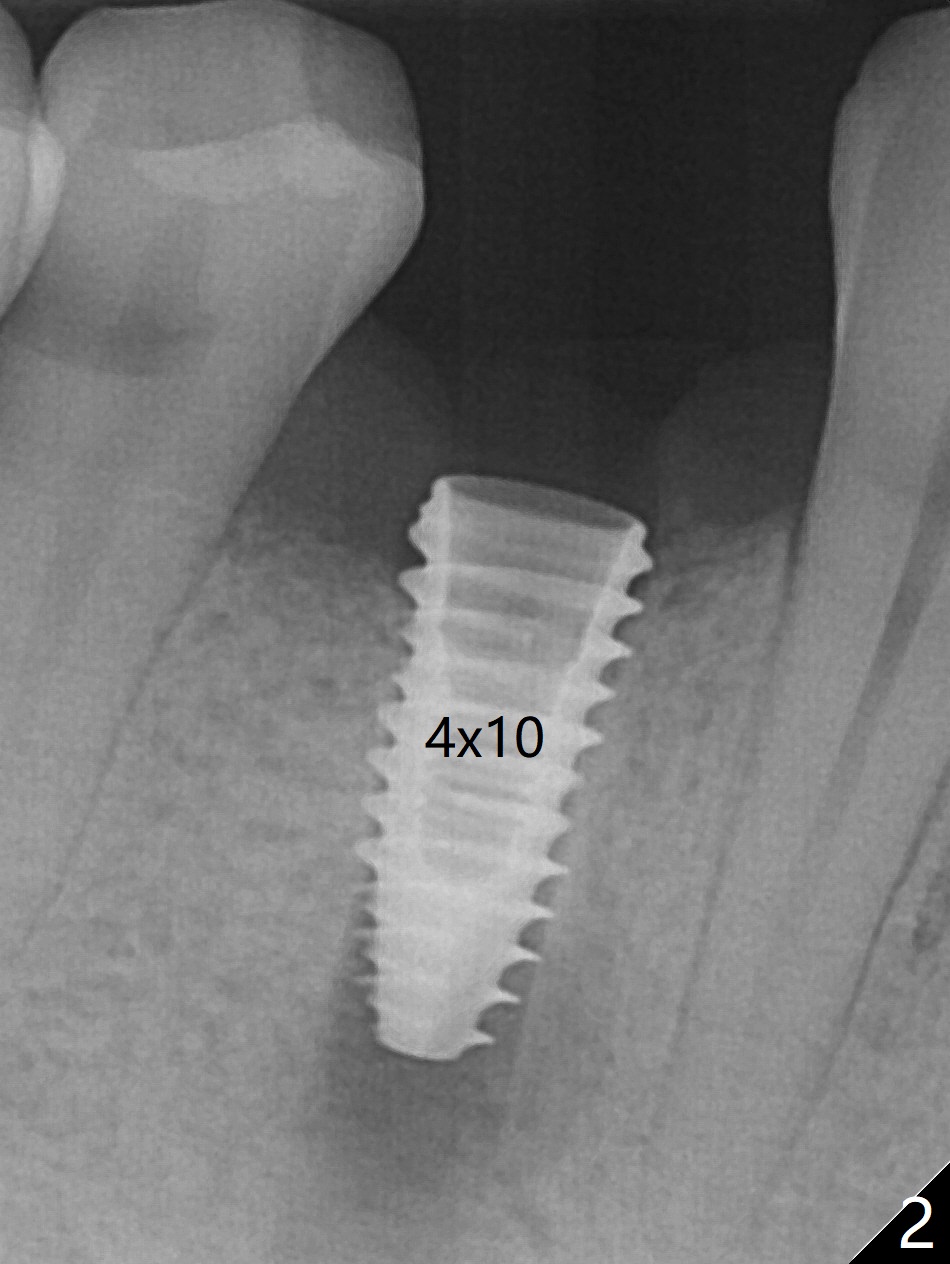

Immediately post extraction and curettage of the large buccal apical lesion, osteotomy is established in the lingual wall of the socket of #28 (slightly distal) for 17 mm vs. 15 mm socket depth (Fig.1 (red line: Mental Loop)). Following sequential osteotomy until 3.5x17 mm drill, a 4x10 mm dummy implant is partially placed with stability (Fig.2,3 (root measurement: mesiodistal 4 mm; buccolingual 7 mm)). A final implant (4x11.5 mm) is placed with insertion torque of 60 Ncm (Fig.4,5). Since the buccal crest is lower with the buccal gingival recession, the implant is intentionally placed deep as well as lingually so that autogenous bone and Vera graft mixture will be placed in the buccal gap (Fig.6 * (gauze at the moment)). The apical lesion decreases 4.5 months postop (Fig.7). Immediate implant and immediate provisional keep the papillae (Fig.8 *), but cannot prevent the buccal plate from atrophy (Fig.9 *). It appears that socket shield is able to accomplish the latter. The bone density next to the coronal threads increases 10 months post cementation (Fig.10 *) and seems to have continued to do so 1 year 4 months post cementation (Fig.11).